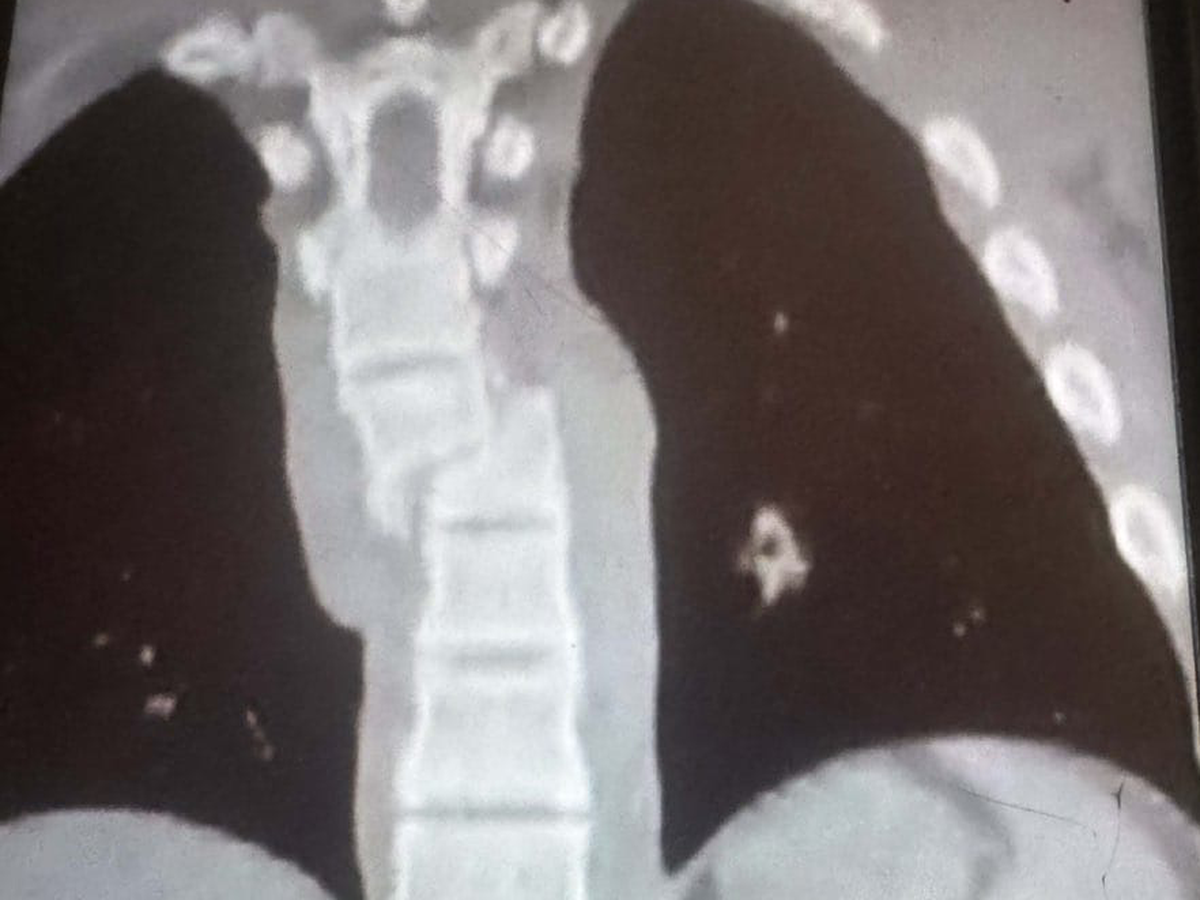

Zusätzlich erlitt er eine gebrochene Rippe und eine schwere Verletzung der Lunge. Durch ein Loch in der Lunge kam es zu weiteren Komplikationen. Seitdem liegt er auf der Intensivstation, sein Zustand ist kritisch und leider zuletzt eher schlechter als besser geworden.